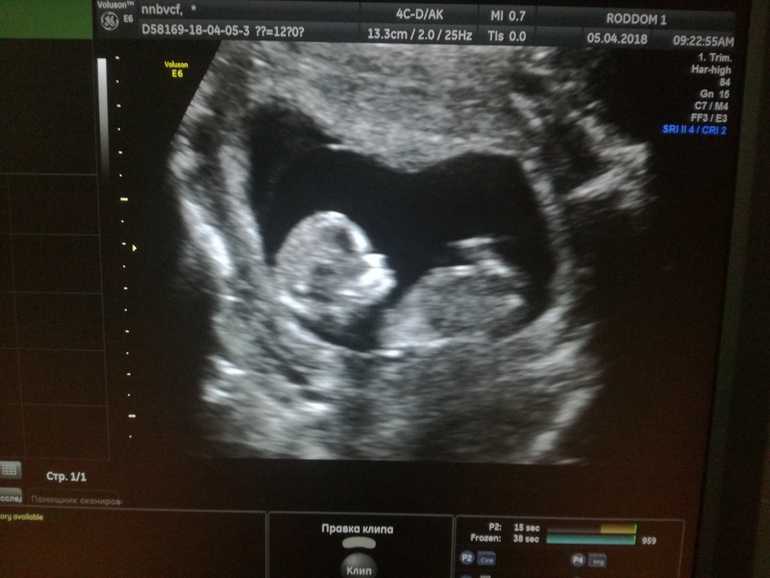

По скринингу идем срок в срок, ровно 12 недель , ктр 59мм, твп 1.2 мм, носик 2.2 мм, чсс 155 уд/мин) хотела узнать кто, но не сказали))) может быть вы предположите?😅😅😅